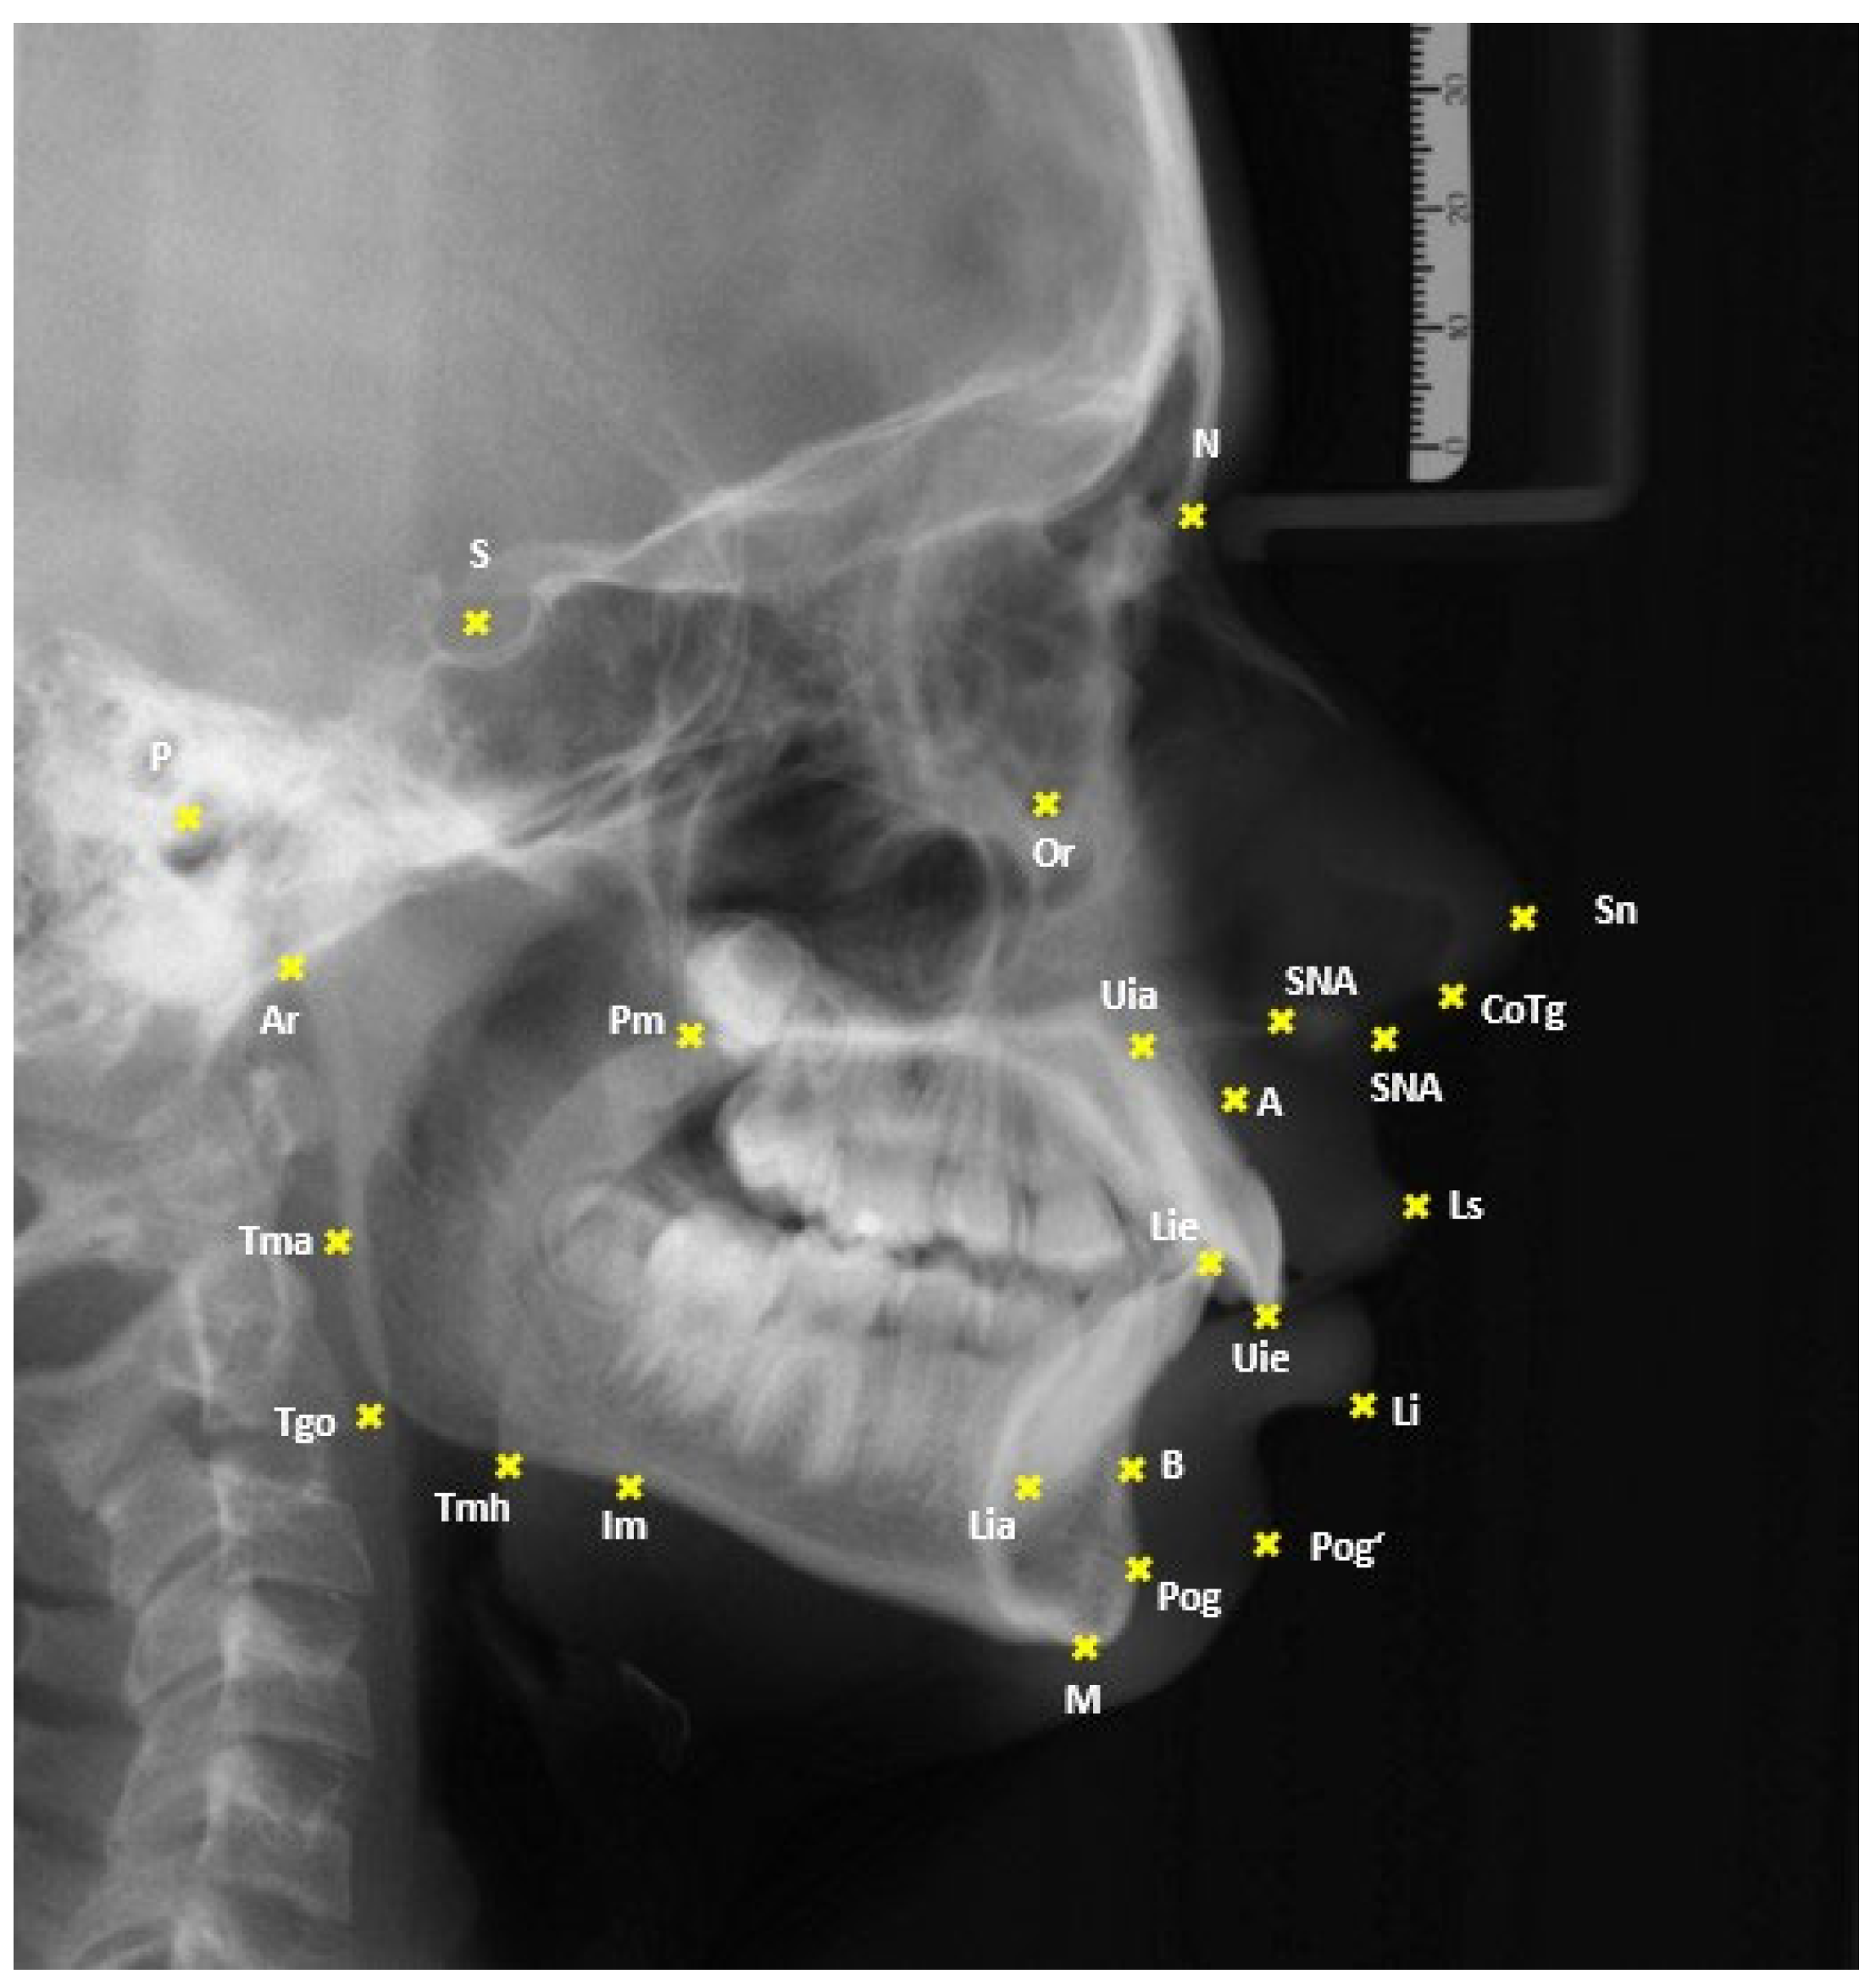

| Landmark/Measurement | Abbreviation | Definition |

|---|---|---|

| Sella | S | Center of the pituitary fossa |

| Nasion | N | Most anterior point along the nasofrontal suture |

| Anterior Nasal Spine | ANS | Tip of the anterior nasal spine |

| Pterygomaxillary Fissure | Pm | Intersection of the posterior margin of the maxillary body with the contour of both soft and hard palates |

| Point A | A | Deepest point of the concavity on the frontal contour of the alveolar process of the maxilla |

| Upper Incisal Edge | Uie | Incisal tip of the most anterior upper central incisor |

| Upper Incisal Apex | Uia | Root apex of the most anterior upper central incisor |

| Lower Incisal Edge | Lie | Incisal tip of the most anterior lower central incisor |

| Lower Incisal Apex | Lia | Root apex of the most anterior lower central incisor |

| Point B | B | Deepest point of the concavity on the frontal contour of the alveolar process of the mandible |

| Menton | M | Lowest point of the mandibular symphysis |

| Masseteric Notch | Im | Point of the deepest cranial concavity of the horizontal mandibular ramus |

| Articulare | Ar | Intersection of the posterior contour of the mandibular condyle with the clivus of the cranial base |

| Tagent Menton Horizontal | Tmh | Tangential point from Menton to the horizontal ramus at the mandibular angle |

| Tagent Menton Ascendance | Tma | Tangential point from Articulare to the ascending ramus at the region of the mandibular angle |

| Gonion Tangential Point | Tgo | Intersection of the lines Me-Tmh and Ar-Tma |

| Porion | P | Most superior point of the external auditory meatus |

| Orbitale | Or | Most inferior point of the bony orbit |

| Upper Lip | Ls | Point of greatest anterior projection of the upper lip |

| Lower Lip | Li | Point of greatest anterior projection of the lower lip |

| Nasal Tip | Ns | Most anterior point of the nasal tip |

| Soft Tissue Pogonion | Pog’ | Most anterior point of the soft tissue chin |

| Subnasale | Sn | Point where the upper lip meets the nasal columella |

| Columella Tangent Point | CoTg | Tangential point from Subnasale to the nasal columella |

| SNA Angle | SNA | This angle is made by the reference lines S-N and N-A; it provides information about the positional relationship of the maxilla to the cranial base. |

| SNB Angle | SNB | This angle is formed by the reference lines S-N and N-B. It allows assessment of the sagittal position of the mandible. |

| ANB Angle | ANB | This angle is formed by the reference lines Nasion-Point A and Nasion-Point B. It provides insight into the sagittal relationship between the mandible and maxilla. |

| Interincisal Angle | UiLi | This angle is built by the axes of the upper incisors (Uie-Uia) and the lower incisors (Lie-Lia). It is measured dorsally and shows the relationship between the axes of the anterior teeth. It is also a good indicator of bimaxillary dental protrusion. A smaller angle indicates more protruded anterior teeth. |

| Upper Incisor Angle | UiSNAPm | This angle is constructed between the axis of the upper incisors and the maxillary plane (Spa-Pm). It provides information about the inclination of the first upper incisors in relation to the basal plane of the maxilla. |

| Lower Incisor Angle | LiMeTmh | This angle is between the axis of the lower incisors and the mandibular plane (Me-Tmh). It shows the inclination of the first mandibular incisors relative to the mandibular plane. |

| Upper Incisor to Nasion Line Angle | UiNS | This angle is formed by the axis of the upper incisors and the NS line. It provides information about the inclination of the first upper incisors relative to the N-S line. |

| Mandibular Incisor to Frankfurt Horizontal Angle | LiFH | This angle is formed by the axis of the lower incisors and the Frankfurt Horizontal (P-Or). It shows the inclination of the first lower incisors relative to the Frankfurt Horizontal plane. |

| Distance Ls-Esthetic Plane | Ls-E | This distance is measured from the upper lip to the Ricketts Esthetic Plane (Ns-Pog‘) at a 90-degree angle. It assesses the harmonious appearance of the lip profile relative to the soft tissue components of the nose and chin. |

| Distance Li-Esthetic Plane | Li-E | This distance is measured from the lower lip to the Esthetic Plane according to Ricketts, vertical to the Esthetic Plane. It also provides insight into the harmonious appearance of the lip profile relative to the soft tissue components of the nose and chin. |

| Distance Ls-SR Line | Ls-SR | This distance is measured from the upper lip to the SR Line (a perpendicular to the Nasion–Sella line, minus seven degrees at the Sella). It helps in evaluating the lip position relative to a bony reference plane. |

| Distance Li-SR Line | Li-SR | This distance is measured from the lower lip to the SR Line (a perpendicular to the Nasion–Sella line, minus seven degrees at the Sella). It helps in evaluating the lip position relative to a bony reference plane. |

| Nasolabial Angle | LsSnCoTg | This angle is formed by the upper lip tangent (Ls-Sn) and the columella tangent (Sn-CoTg).42 It gives information about the upper part of facial convexity, specifically the prominence of the upper lip in profile. |

| Anterior Face Height | AFH | This distance is measured from the Nasion to the Menton. It describes the anterior facial height. |

| Posterior Face Height | PFH | This distance is measured from the Sella to the Gonion Tangent Point. It describes the posterior facial height. |

| Facial Height Ratio | S-Tgo/N-Me | This is calculated using the formula Ratio = (Distance S-Tgo * 100)/Distance N-Me. The ratio indicates the proportion of posterior to anterior facial height. |